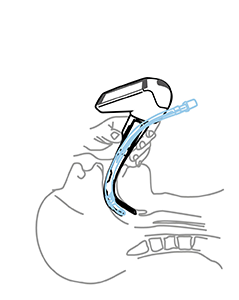

MacIntosh Blade in the Vallecula (preferred)

Airtraq allows both techniques

Macintosh style is the preferred option since it requires less upward traction and therefore it is softer on patient tissues.

If the Airtraq is already underneath the epiglottis and the user prefers to intubate Macintosh style withdraw the Airtraq until the epiglottis falls and advance the tip of the blade into the vallecula.

Miller Blade underneath Epiglottis